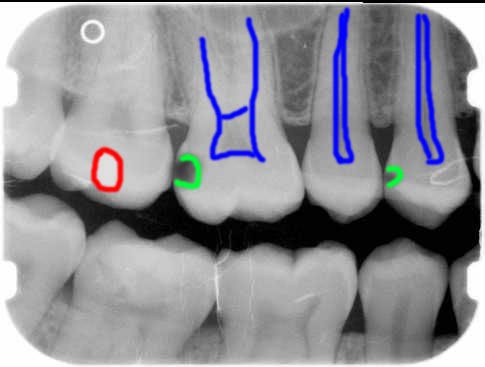

Überall wo Röntgen Strahlen leicht hindurch gehen wird das Bild dunkel, dort wo die Röntgenstrahlen abgehalten werden, wird das Bild hell. Sie sehen ein Zahnröntgen, darunter das gleiche nur mit Erklärungen:

[*]rot umrandet die Füllungen (die sind aus Metall – Röntgenstrahlen gehen schwerer hindurch – Bild wird hell)

[*]blau umrandet der Zahnnerv, dort ist Bindegewebe, weniger Zahnhartsubstanz, also entsteht ein dunkler Schatten …

[*]grün umrandet sehen Sie zwei dunkle Flecken, dort gehen die Röntgenstrahlen leichter hindurch – wieso?

Weil dort weniger Zahnhartsubstanz ist, sprich die Kariesbakterien haben dort den Zahn aufgelöst … so sieht also Karies aus, ein dunkler Fleck.

Auf Ihrem Bild würde ich mir die grün umrandeten Zähne genauer ansehen – wobei eine Bewertung via Web sehr eingeschränkt möglich ist …